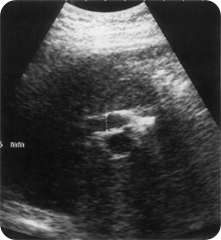

ULTRASOUND IMAGES BILIARY DILATATION WITHOUT JAUNDICE

Ultrasound images Postsurgical CBD dilatation In patients who have had cholecystectomy associated with previous dilatation of the CBD it is common to find a persistent (but non-significant) mild dilatation of the duct postoperatively. The serum alkaline phosphatase and bilirubin levels should be normal in the absence of pathology. Because stones may be found in the duct postoperatively, it is important to differentiate non-obstructive from truly obstructive dilatation in a symptomatic patient (Fig. below). If in doubt, the patient may be rescanned at a suitable interval to assess any increase in ductal diameter.

Biliary dilatation following laparoscopic

cholecystectomy, due to a surgical clip across the CBD